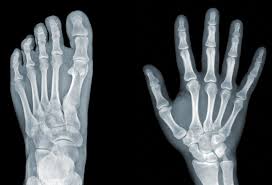

Hand & Foot

Specialized surgeries to relieve pain and correct hand or foot conditions.

Carpal Tunnel Release

Surgical release of pressure on the median nerve by cutting the transverse carpal ligament.

Purpose: To relieve numbness, pain, and tingling in the hand.

Steps: Small incision → Ligament division → Nerve decompression.

Trigger Finger Release

Cutting the tendon sheath to allow smooth tendon movement in the finger.

Purpose: To relieve locking or stiffness of the finger.

Steps: Small incision → Release of A1 pulley → Wound closure.

Toe Osteotomy

Realignment of toe bones by cutting and repositioning them.

Purpose: To correct deformities like hammer toes or bunions.

Steps: Bone cutting → Fixation with screws/pins → Healing phase.

Exostosis (Bone Spur) Removal

Removal of bony growths that cause pain or pressure in the foot.

Purpose: To relieve discomfort and improve walking.